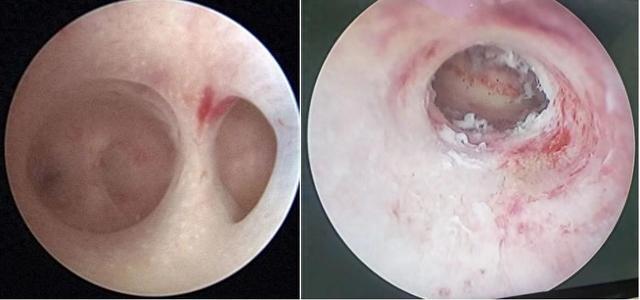

▲图为宫腔镜下的宫腔粘连

宫腔镜术后预防再次粘连的措施也是至关重要的。手术可以将子宫内膜的粘连带去除,或者将瘢痕切除,恢复正常的宫腔形态,如果术后未采取任何预防再次粘连的措施,宫腔很快就会发生再次粘连。